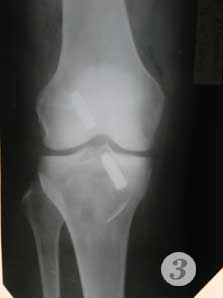

2,3 - после операции пластики передней крестовидной связки коленного сустава